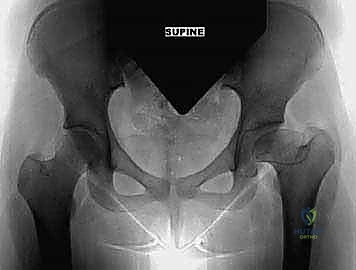

1. الأشعة السينية الرقمية (Digital X-rays): يتم أخذ صور بوضعيات متعددة (أمامية خلفية، ووضعية الحوض الكاذبة False Profile). يقوم الدكتور هطيف بقياس زوايا دقيقة جداً مثل "زاوية مركز وحافة ويبرغ" (Center-Edge Angle of Wiberg) و"زاوية سقف الحُق" (Tönnis Angle) لتحديد درجة خلل التنسج بالضبط.

3. التصوير المقطعي المحوسب ثلاثي الأبعاد (3D CT Scan): وهي التقنية الأهم في التخطيط لجراحة كياري. تتيح للدكتور هطيف بناء نموذج ثلاثي الأبعاد لحوض المريض على الكمبيوتر، مما يمكنه من محاكاة الجراحة وتحديد زاوية القطع العظمي بدقة متناهية قبل دخول غرفة العمليات.